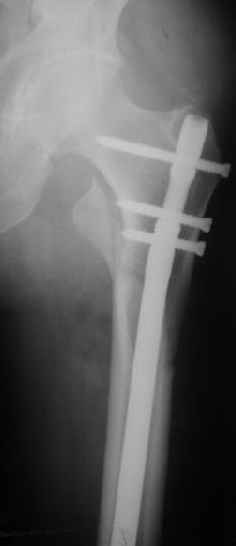

При межвертельных переломах с цефаломедуллярными гвоздями бывает, что проксимальый винт проходит или черед периферический отломок, или прямо над ним. И если остался диастаз, то этот винт при осевой нагрузке не дает сблизиться отломкам. Пример такого остеосинтеза в застарелом случае в приложении.

В качестве предупреждающей меры можно долотом разрушить латеральную стенку дистального отломка под винтом.

В частности, на проксимальном конце сделано еще одно дополнительное статическое отверстие. Можно ввести в проксимальном отделе 4 винта, из них 3 статические (2 в круглые отверстия и 1 по нижнему краю овального). Картинки в приложении. На дистальном конце стержня тоже кое-что улучшено. Спрашивайте в аптеках, как говорится. Выпускается предприятием "ЦИТО" (Москва), то есть это малобюджетное решение.

Это было года 2,5 назад, мы тогда еще уточняли возможности шинирования с угловой стабильностью гвоздем с поперечным расположением винтов при переломах проксимального отдела бедра. Пациенту не пришлось приобретать намного более дорогой рекон или проксимальный гвоздь. В приложении еще несколько примеров применения того гвоздя при высоких переломах бедра, в том числе с более латеральной точкой входа. Гвоздь изгибаем для этого.